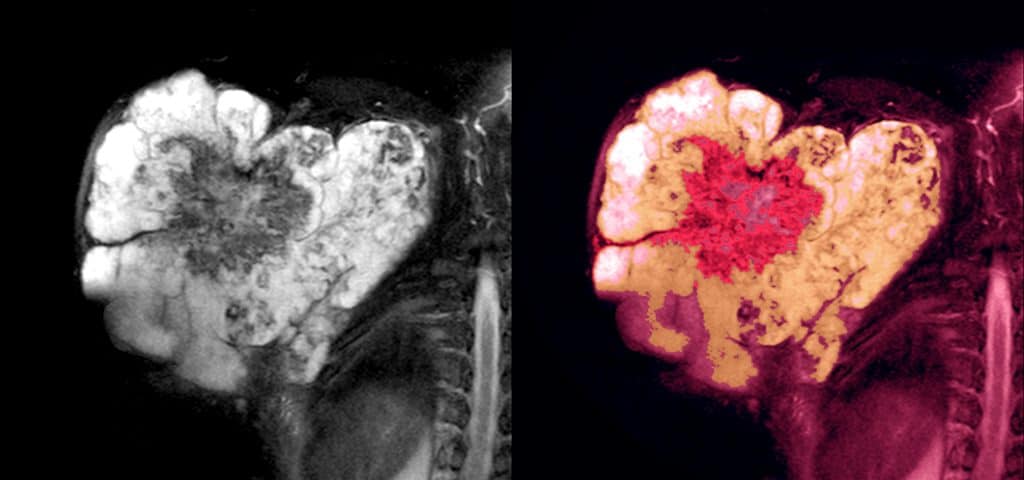

Kako bi se postiglo adekvatno liječenje, sarkomi mekog tkiva zahtijevaju dijagnostičke pretrage koje daju uvid u evoluciju tumora. Važno je uzeti u obzir kliničko stanje bolesnika, dob i stadij bolesti. U ovom slučaju postoji isti protokol kao i kod drugih vrsta malignih tumora, a to su: anamneza i klinički pregled, zatim slikovne pretrage, kompjuterizirana tomografija, magnetska rezonancija i biopsija. Liječenje se provodi operativno. Ovisno o slučaju, može biti potrebno daljnje liječenje.